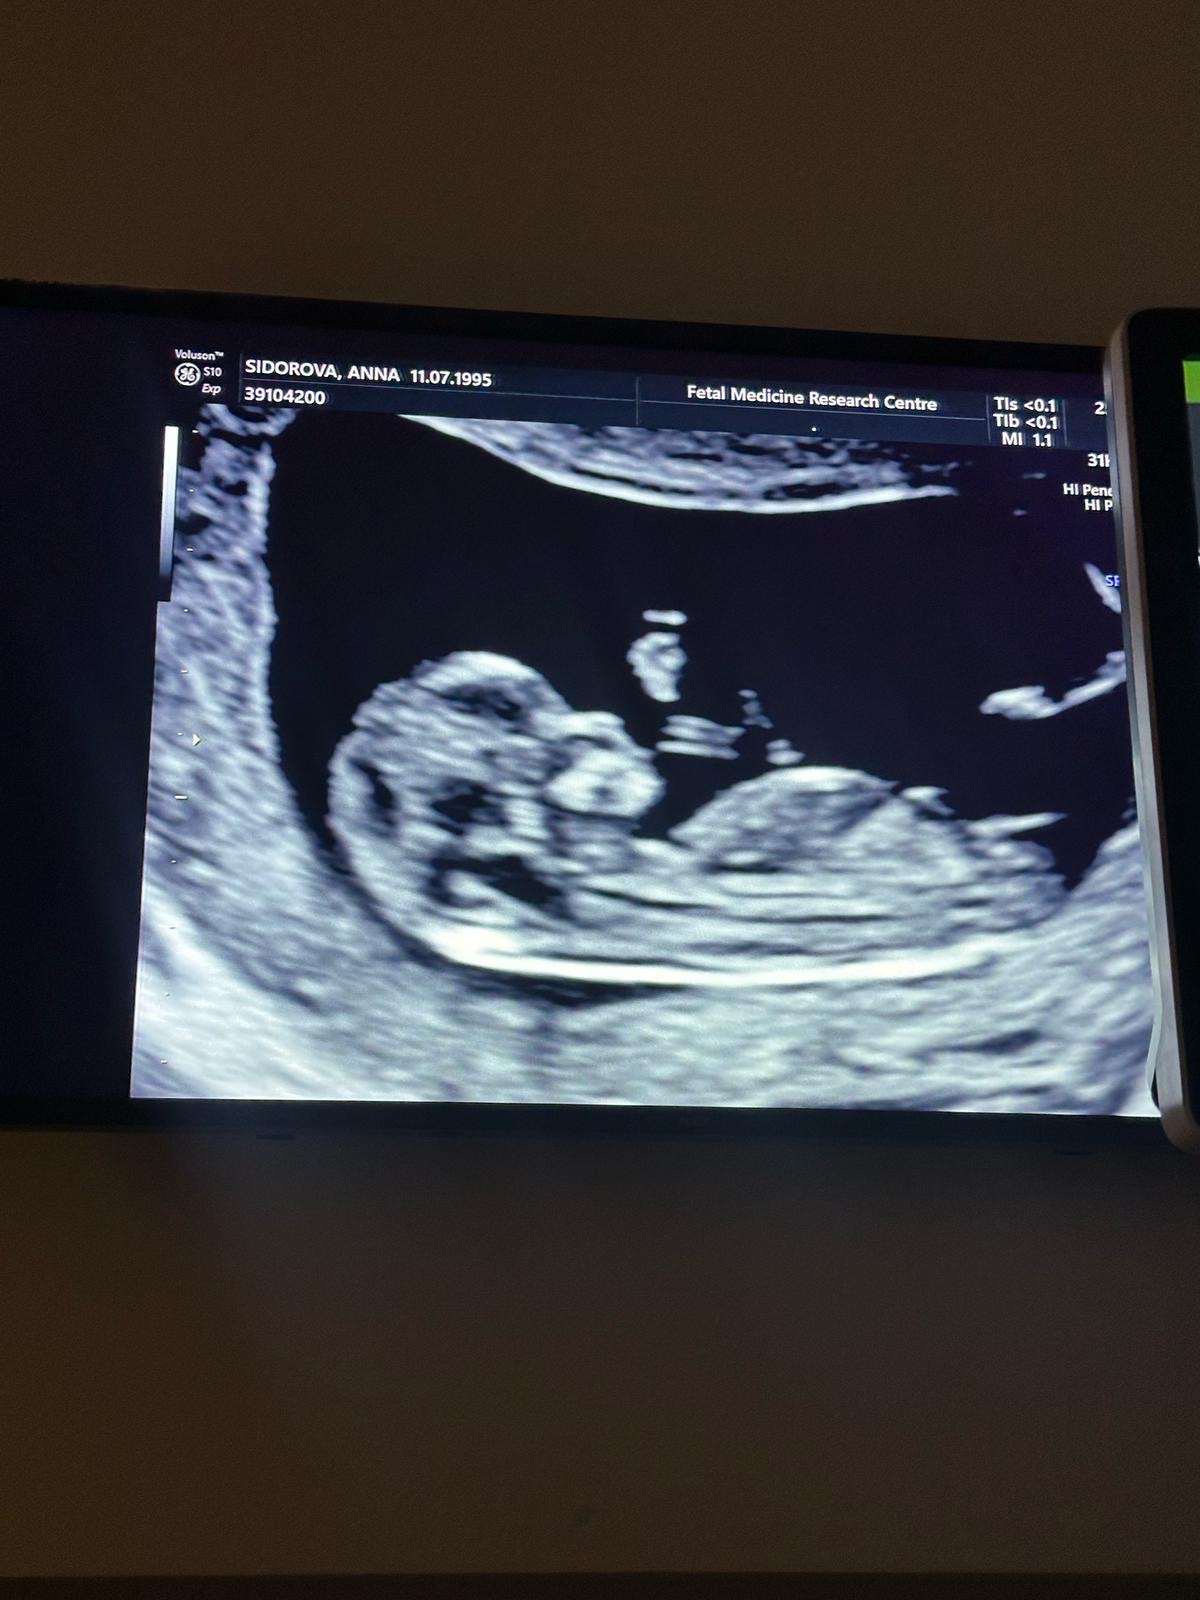

Пол малыша

Это девочка 😁

Девочка )

Скрининг в 13,5 недель в МедЭксперт. Пол двойни❤️💙